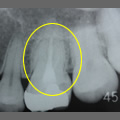

抜髄症例

主訴:3日前から何もしなくても前歯が痛む

- 虫歯が大きく神経まで達している為、虫歯を除去し抜髄

- ファイルを使って根の長さを測定・根管形成(根管-神経が入っていた管-を根管充填しやすい形に整えること)

- 根管充填剤が根尖(根の先端)まできっちりと充填